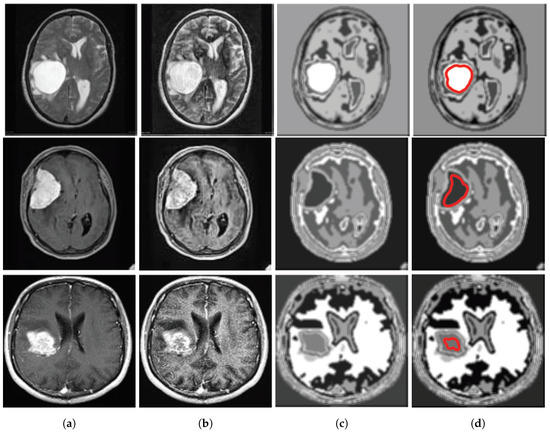

A database of 40 brain tumor images is shown in Figure 2a,b where the first 20 images are shown in Figure 2a and the next 20 images are shown in Figure 2b. The database has been made by collecting different complex brain tumor images. We collected these images from [17,18,19] and pre-processed for the betterment of application in our algorithmic program.Then, we have processed these images by MATLAB 2016(a) and made the database for final use shown in Figure 2a,b. The tumors in these images are so critical that it is too hard for the common people to detect it so easily.

Figure 2.

Database of 40 brain tumor MR image. (a) The database of first 20 brain tumor MR image. (b)The database of next 20 brain tumor MR image

Figure 5.

(a) Input images for TKFCM, (b) Segmented images from the 1st segmented algorithm (TK-means) with no. of gray level = 8, (c) Further enhancement of the segmented image, (d) Detected brain tumor images from the TKFCM.